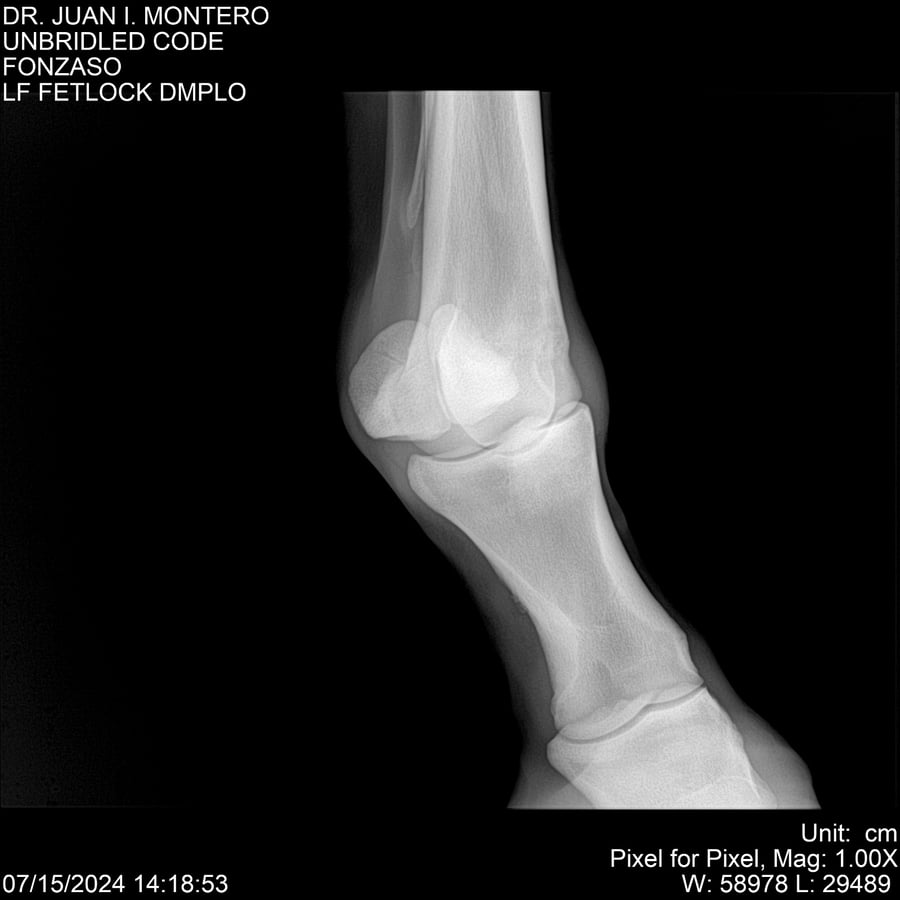

• Empresa: Abelenda N. R., Walter Hugo